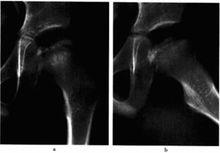

股骨頭骨骺缺血性壞死圖9-2左股骨頭骨骺缺血性壞死(進展期)a,b.平片,示左股骨頭骨骺變扁,密度不均勻增高並夾雜囊變透亮區,關節面欠光整.關節間隙稍增寬

3左側投骨頭骨骺缺血性壞死(進展期)圈9-3左側投骨頭骨骺缺血性壞死(進展期)

a.b平片,示左股骨頭骨骺密度變扁、碎裂,密度不均勻增高,乾骺端稍增寬